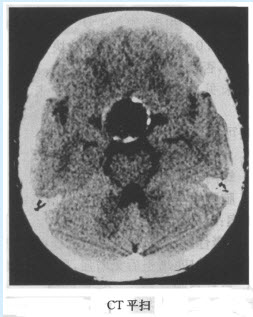

患者,男,56岁。因背部疼痛2个月入院;查体:胸椎T~T棘突和椎旁有压痛,胸椎活动受限。体温38.4℃,X线平片和CT见下图。

(单选题)首先考虑为何种疾病()

(多选题)下列哪几项支持诊断()

(多选题)对于此病的特点,下列哪几项正确()